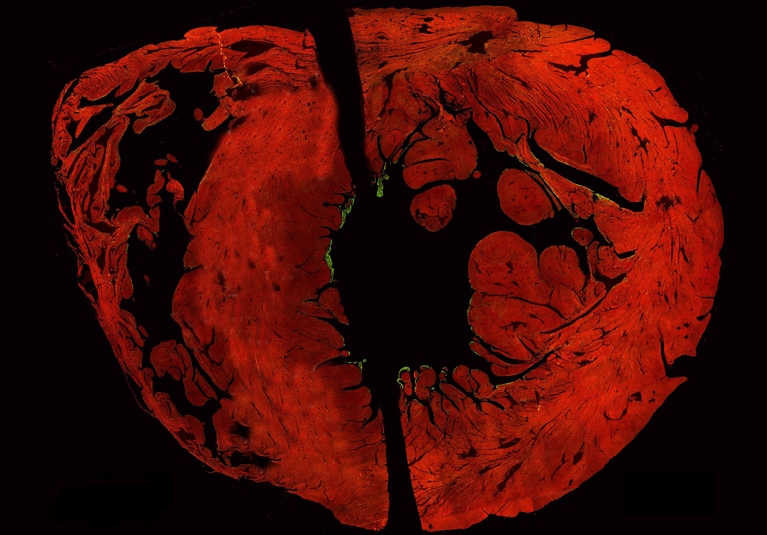

With the reliance on animal analogies and nonspecific markers in prior studies, the depth and complexity of human PF distribution was underestimated. "The finding was enabled by whole-mount megablock cross-sectional analysis of human hearts," says Dr. Behfar. "The study originated from comparative transcriptomics on 10 human hearts, identifying 99 upregulated genes in PF-rich regions, with MYL4 emerging as a top candidate for its specificity to conductive myocardium."

"This study presents a key discovery: A deep-seated network of transmurally intercalated, MYL4-positive PFs within the human ventricular myocardium, which accounts for over 60% of the total myocardial PF content. Traditionally, PFs have been understood as being primarily restricted to the subendocardial layer (the inner surface of the heart muscle), based largely on animal models and historic human histological data," says Dr. Behfar. "However, using advanced transcriptomics and immunostaining with the novel biomarker MYL4, we were able to visualize and quantify an extensive intramural PF network that extends deep into the myocardium, intercalating with working cardiomyocytes."